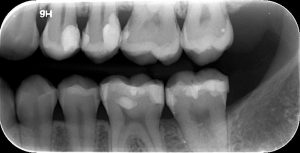

2. FULL-MOUTH ΟΠΙΣΘΟΦΑΤΝΙΑΚΕΣ  ΑΚΤΙΝΟΓΡΑΦΙΕΣ

Πρόκειται για ένα σετ 14-16 οπισθοφατνιακών ακτινογραφιών, οι οποίες λαμβάνονται διαδοχικά προκειμένου να απεικονιστούν όλα τα δόντια της άνω και κάτω γνάθου.